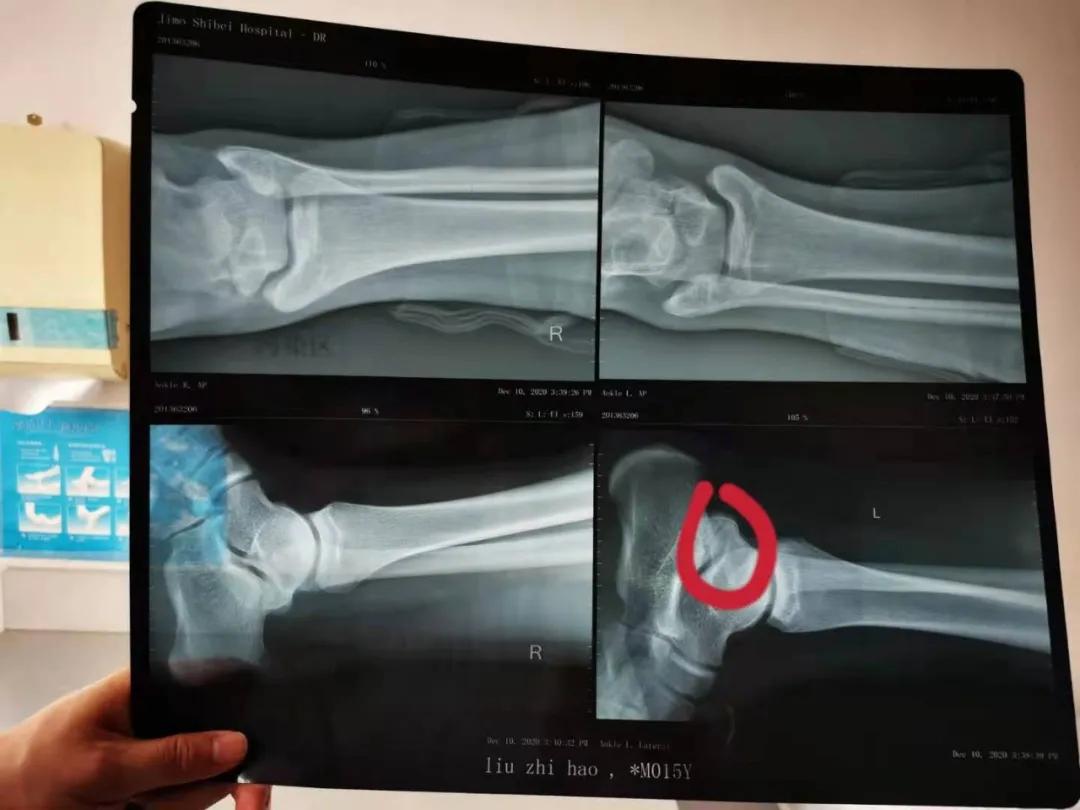

疾病诊断:经过我们仔细检查身体,再配合X光的检查,才发现原来是跟距骨桥。以我多年的临床经验发现,这么胖的孩子跟距骨桥有症状,很多人都是因为痛风,就是血尿酸高。

经过检查,病人BMI指数27.7属于肥胖,而且果然这个孩子的血尿酸达到650以上,基本上确诊是痛风引起的跟距骨桥部位的疼痛,要治疗的话还是先治疗这个痛风,降尿酸,然后跟距骨桥如果还持续有症状是可以做手术切除的。